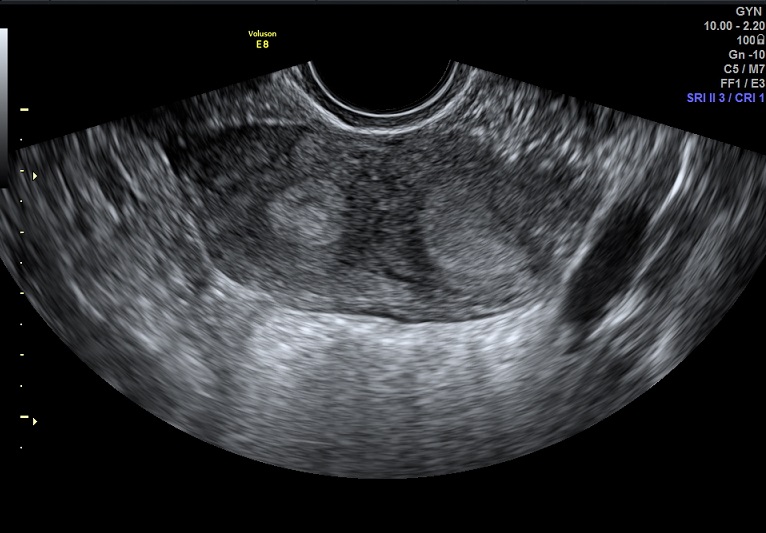

女性,25岁,原发性不孕2年,有子宫畸形病史,畸形类型不详。常规二维超声子宫横径增宽,宫底部横切面内膜不连续,动态扫查似显示为Y型。宫腔三维显示:两侧宫角分开成Y型,内膜凹陷达到宫颈内口。诊断:完全中隔子宫。